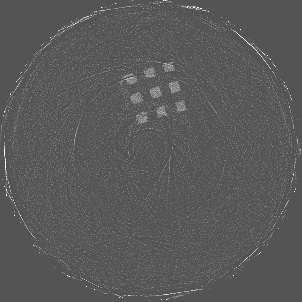

Figure 7 shows a single slice spectral reconstruction of the Mg scaffold. Due to low atomic number of Mg (Z = 12) compared to Ti (Z = 22), the results did not exhibit any significant beam hardening effects. Low energy reconstruction shows good spatial information while high energy ranges are limited by photon noise. In scans involving smaller samples made from low-Z materials like Al or Mg, acquiring low energy quanta in CSM provide high spatial information with minimum or no beam hardening effects. Figure 8 illustrates a single slice spectral reconstruction of the Ti mesh. Similar to the Ti scaffold, streaks are less pronounced in the mid and high energy ranges.

Refer to caption

(a) 15 to 80 keV

(b) 35 to 80 keV

(c) 55 to 80 keV

(d) 62 to 80 keV

Figure 7: Spectral reconstruction of Mg scaffold. Low energy ranges provide good spatial resolution while high energy ranges are limited by photon noise.